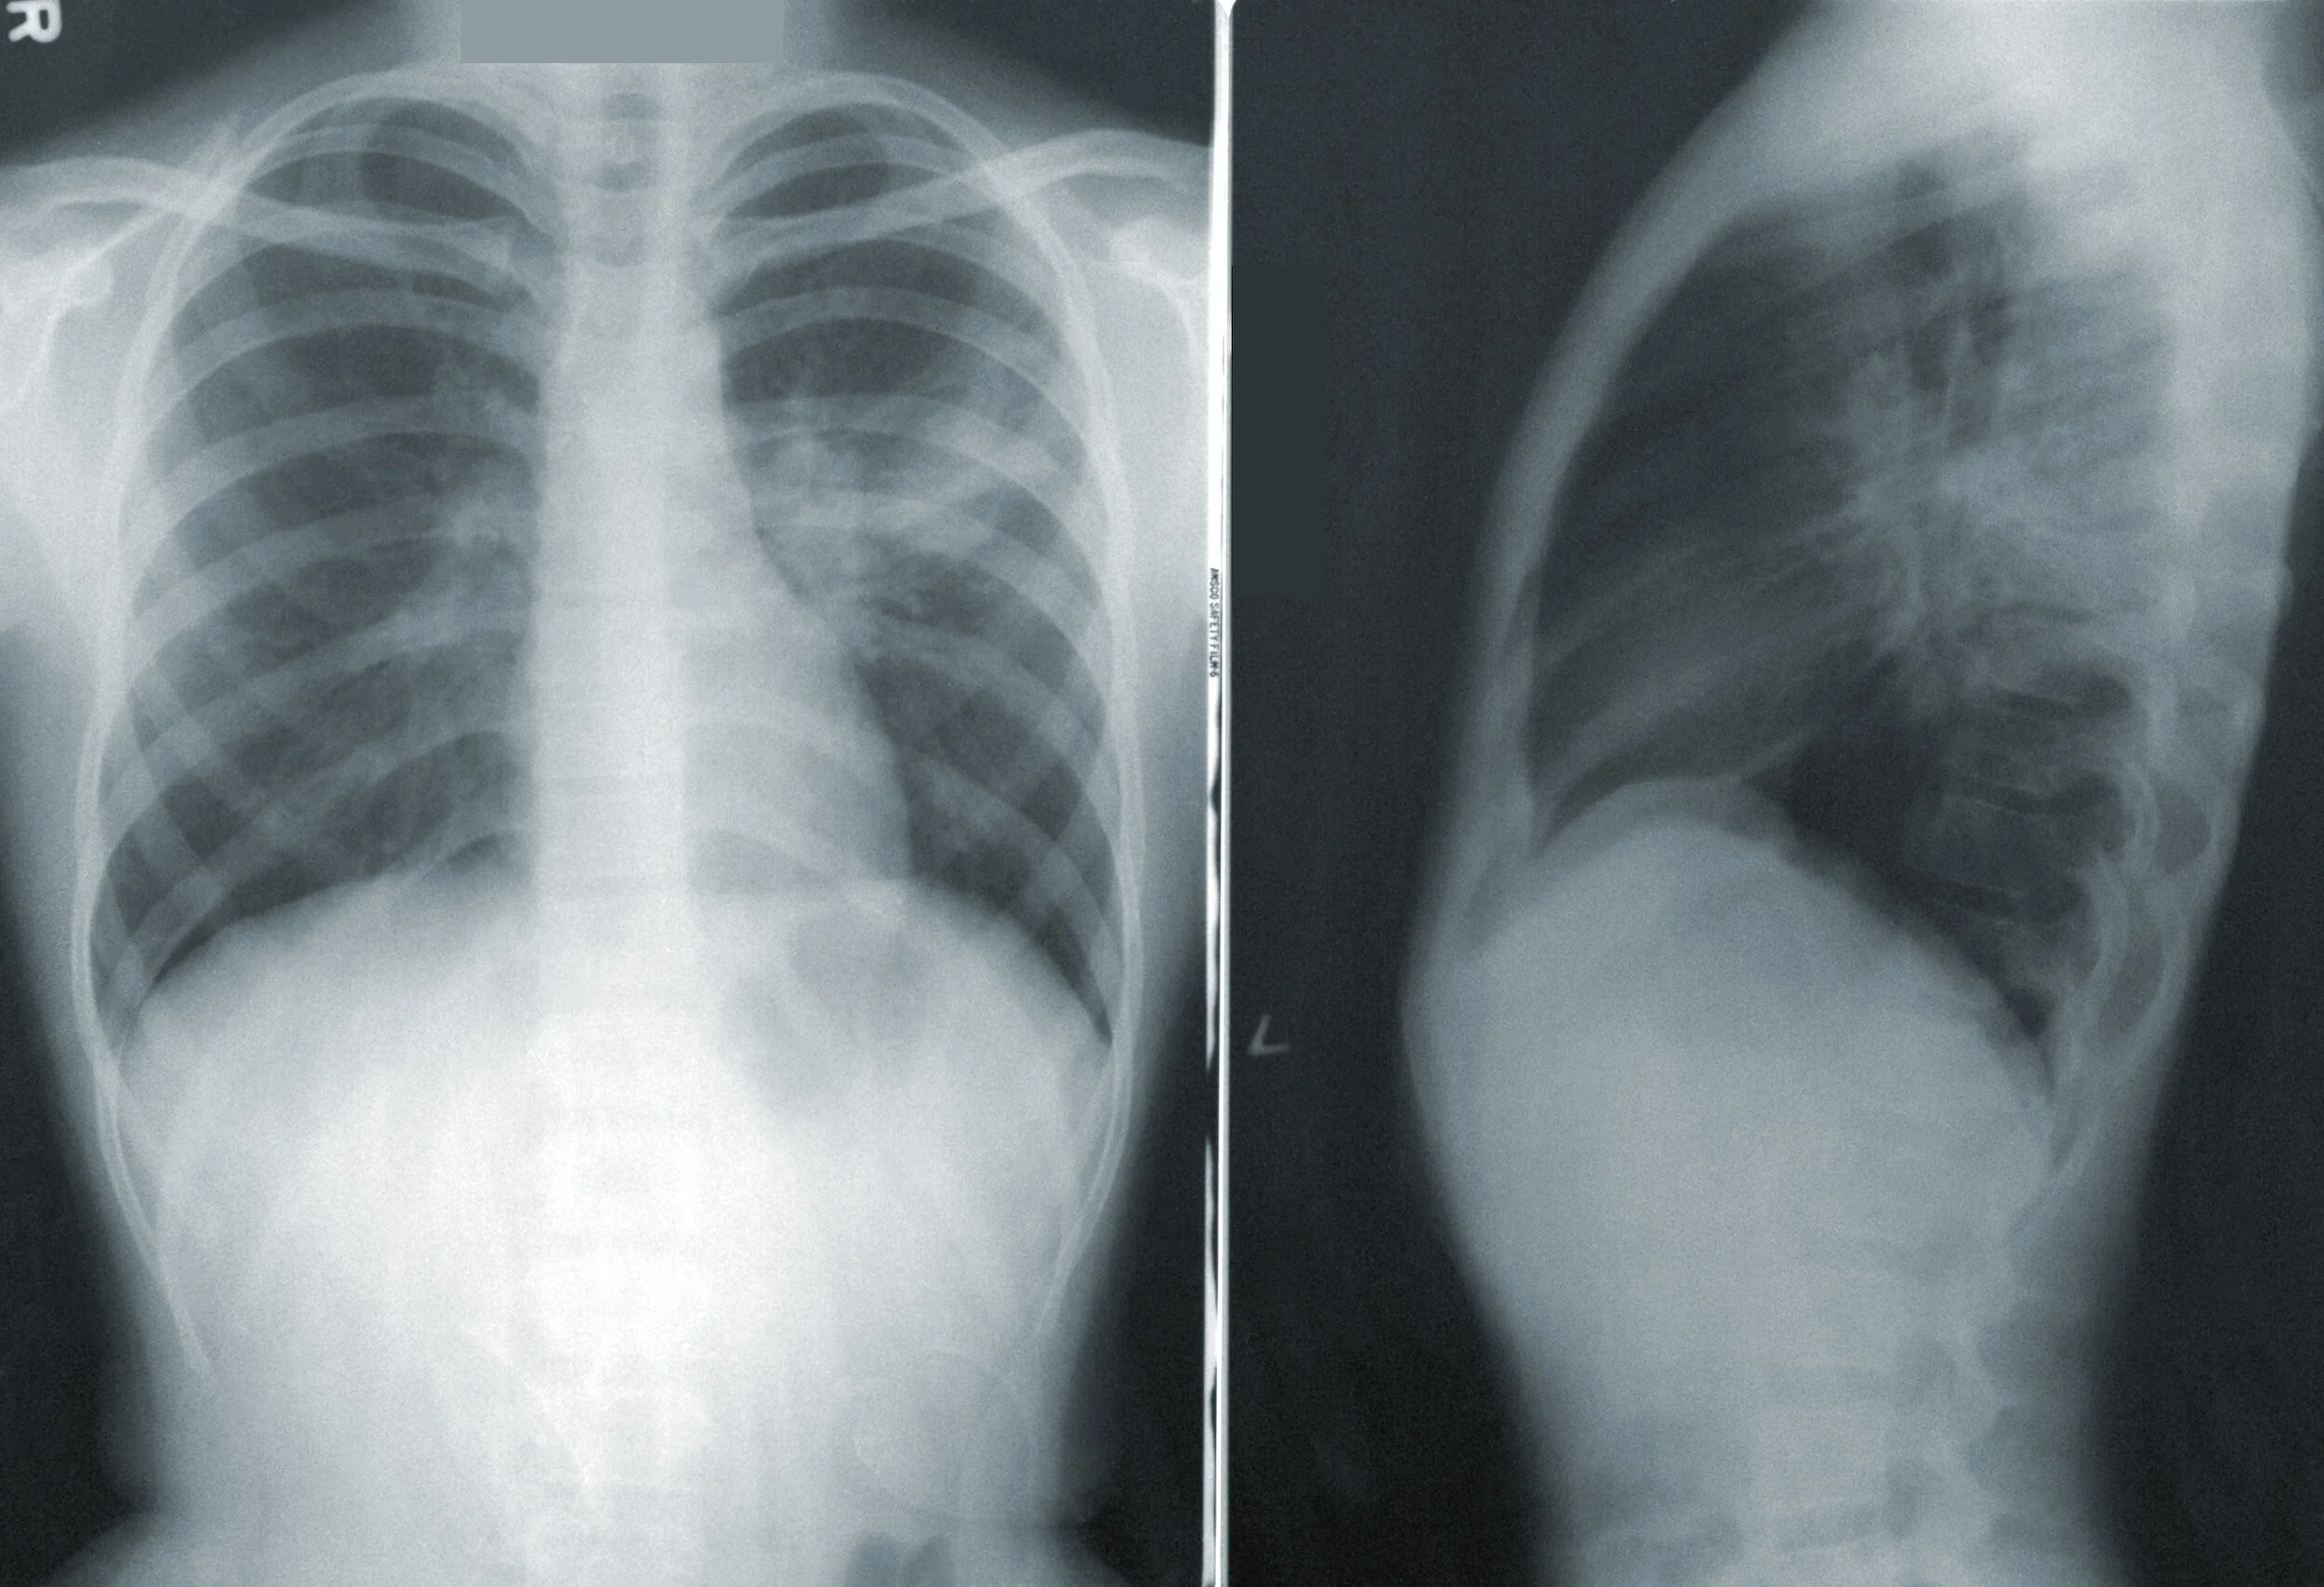

X-rays, or radiographs are an important tool a Chiropractor can use to rule out conditions that would make an adjustment contraindicated. The decision to take X-rays should be based on a proper history and exam of the patient. After 25 years in practice, experience has shown me far too often this decision made by some Chiropractors is for the wrong reasons.